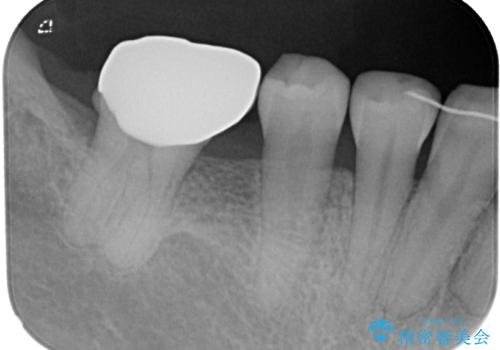

矯正装置を長いこと付けていたことで、歯が大きく捻転してしまい、舌に当たる感覚を気にしていらっしゃいましたが、補綴治療により捻転とともに解消することができました。

上顎の最後臼歯と咬み合わせるために前後径が大きくなっており、歯肉周りに汚れが溜まりやすくなるため、日々の清掃と定期的なクリーニングが必要となります。